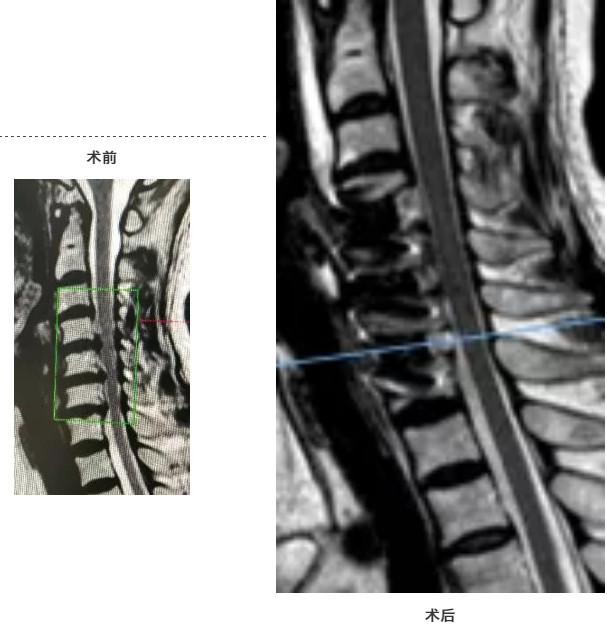

拍摄颈椎CT及MRI后,明确诊断为颈椎间盘突出并局灶性后纵韧带骨化,脊髓明显受压。

为了尽量保留患者颈椎椎体及活动节段,避免椎体切除术后放置钛网引起下沉及植骨不融合问题,经过反复讨论和研究后,何主任大胆提出采用改良经椎间隙椎体次全切除局灶性后纵韧带骨化切除并采用大号Zero-Plate(零切迹)内固定术治疗。

采取前路改良经椎间隙椎体次全切除局灶性后纵韧带骨化切除、采用大号Zero-Plate(零切迹)内固定术治疗后纵韧带骨化症,有以下优势:

1、起到了良好的减压效果 2、避免了过多的切除颈椎 ,造成重建困难、植骨不融合、椎体塌陷等问题 3、手术出血量减小,减轻了对患者的损伤,利于术后恢复